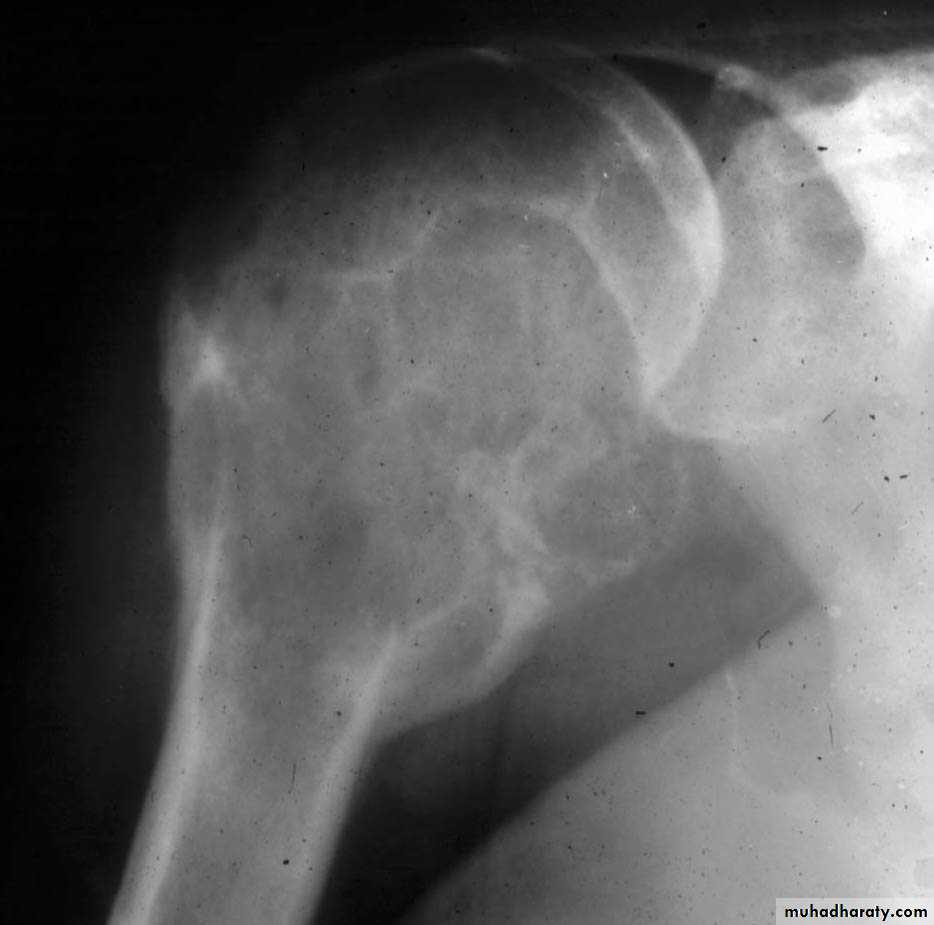

Malignant potential : 5%Osteosarcoma

Commonest primary malignant bone tumour in child

Highly malignantHistology : malignant cells

producing osteoid10% metastasis at presentation

C/FAge : 10 -25 yr

Pain : constant & more at night

SwellingPathologic # : rarely

XRMetaphyseal lesion

Usually around the knee

Osteolytic & osteoblastic areas

Soft tissue invasion sun-ray appearancePeriosteal elevation Codman`s triangle

Rx

CT + surgery

5 yr survival : 60 %